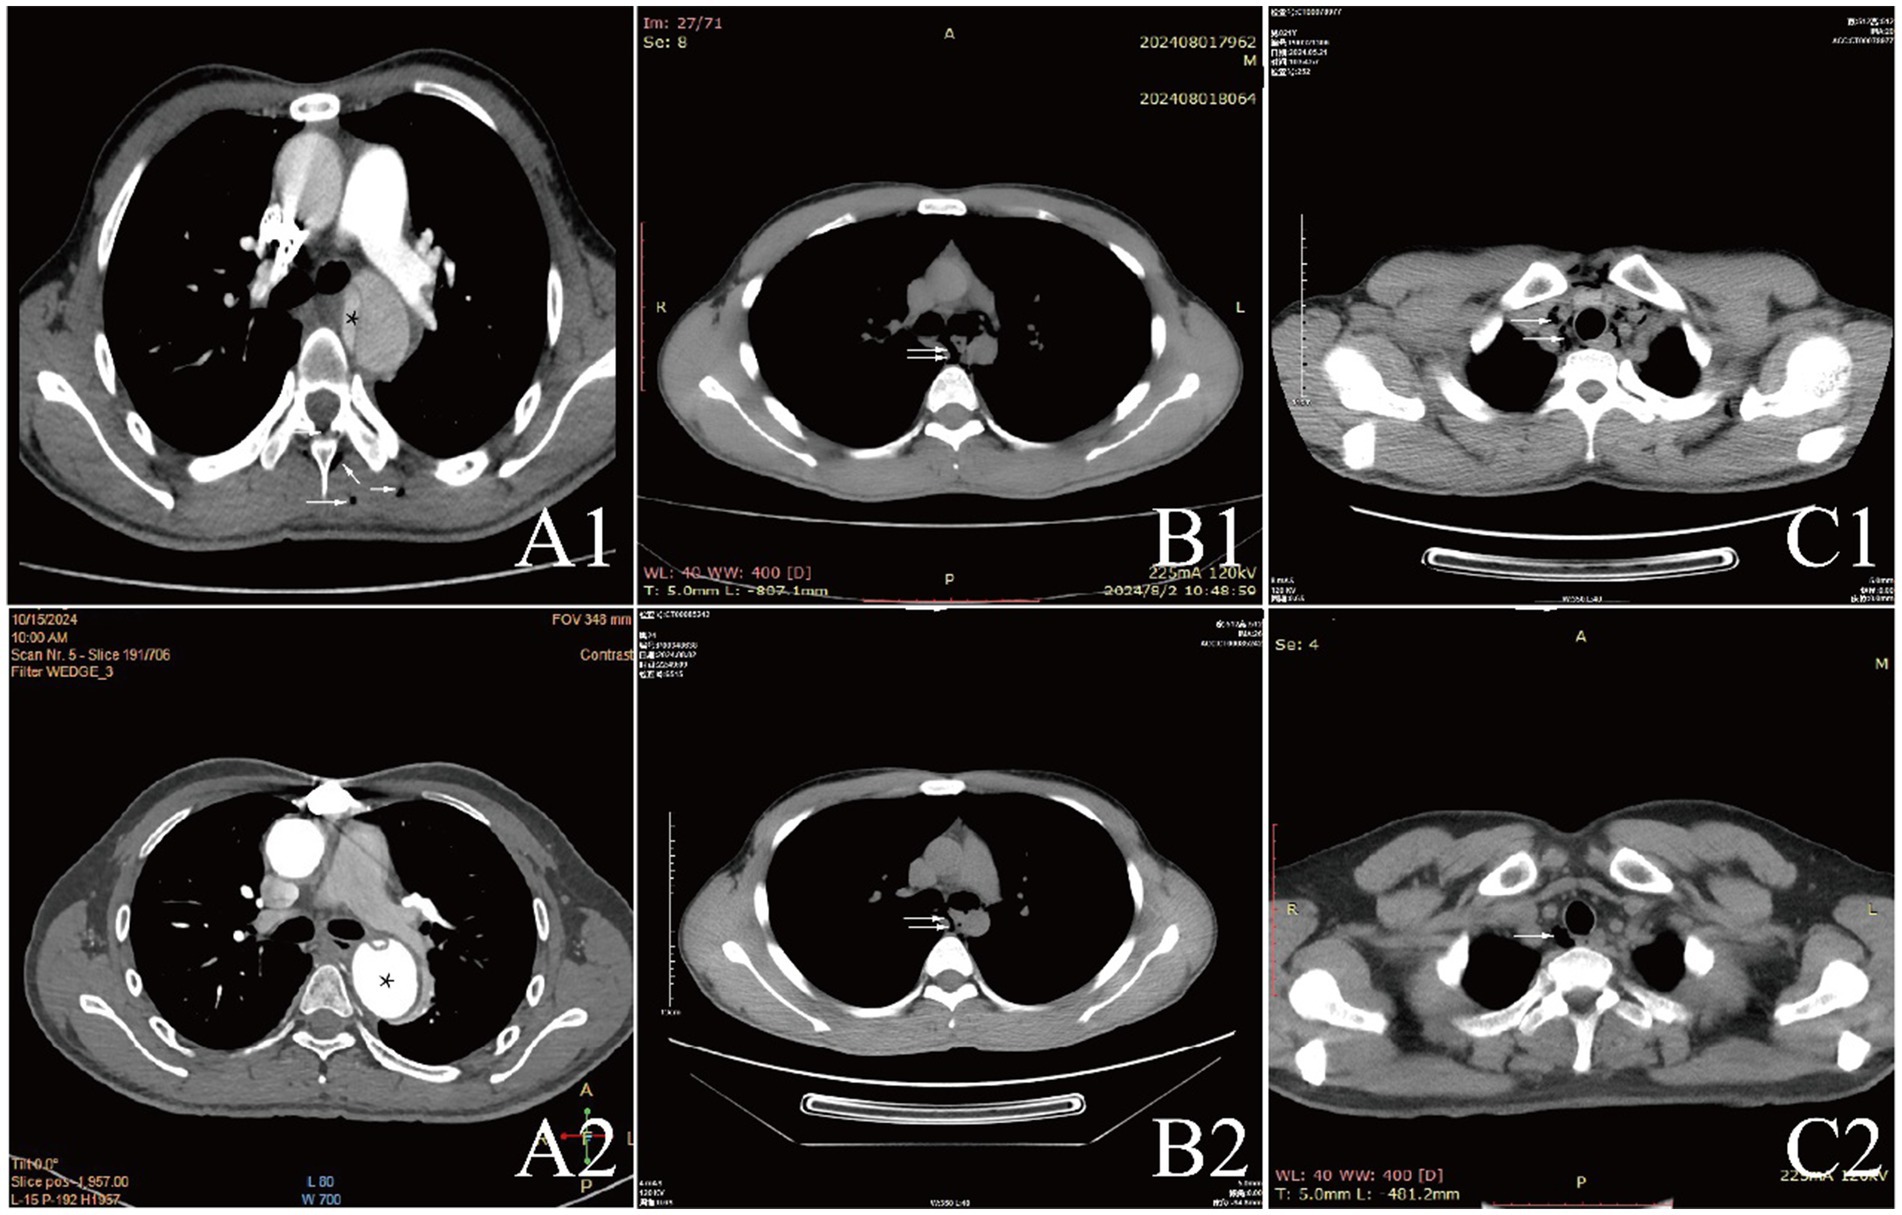

Examinations affected by the hypoxic environment of high altitudes, all patients exhibited varying degrees of increased red blood cell count, hemoglobin concentration, and uric acid (UA). Case 6 and 7, who were diagnosed with acute appendicitis and pulmonary infection, respectively, showed increased percentages of neutrophils. Case 1, in the acute phase of aortic dissection, also had an elevated white blood cell count. Additionally, we observed that D-dimer in the blood is a good indicator of myocardial or vascular damage. It showed varying degrees of elevation in patients with aortic dissection, while this indicator remained normal in other patients, maintaining a high negative predictive value. It is noteworthy that the serum potassium (K+) levels of all patients were high, with five patients having levels above the normal range. The average serum K+ level for all patients was 5.39 ± 0.73 mmol/L, this may be due to the increased metabolism in high altitude areas (Table 3). The diagnosis of extra-pulmonary emphysema for all patients was confirmed through CT examination. Case 1, 2, 3, 6, and 7 showed subcutaneous emphysema, while the others showed mediastinal emphysema. Specific imaging manifestations are shown in Figure 1.

Figure 1. CT comparison images of extra-pulmonary emphysema treatment before and after for Case 1 to Case 3.

All patients were diagnosed with extra-pulmonary emphysema through CT scans, which showed gas infiltration in the mediastinum or subcutaneous tissue. The patient with aortic dissection was urgently transferred to a lower altitude area for “aortic arch artificial vessel replacement surgery.” Case 6 underwent “appendectomy” for treatment, and three patients received antibiotic therapy. All patients were given symptomatic and supportive treatment, including oxygen therapy. Six were given oxygen via a face mask, two received a nasal cannula, and one was assisted with non-invasive ventilation. In addition to case 1, they also received hyperbaric oxygen therapy at 2.0 ATA. Follow-up showed that all patients responded well to the treatment, their conditions improved, and the emphysema was largely absorbed (Figures 1–3).